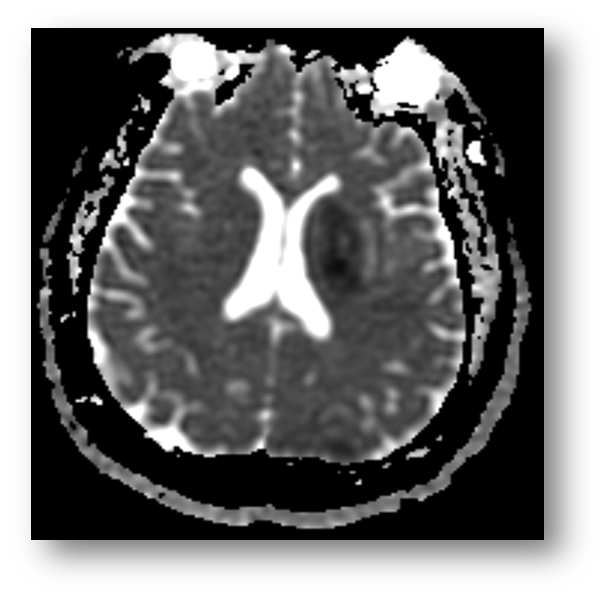

Refer to caption

Figure 3: T2 FLAIR showing hyperintense signal in the PCA and MCA distributions, consistent with acute ischemic stroke. Note that the hypointensity of cerebrospinal fluid due to fluid-attenuation allows for better contrast with the periventricular lesion.

where Mxy(0)subscript𝑀𝑥𝑦0M_{xy}(0) is the transverse magnetization instantaneously after pulse excitation. Following the B1subscript𝐵1B_{1} induction of in-phase precession, the proton spins again begin to dephase according to T2subscript𝑇2T_{2} time constant. Of note, the relaxation of transverse magnetization is faster than the recovery of longitudinal magnetization. In other terms, T2<T1subscript𝑇2subscript𝑇1T_{2}<T_{1}. Figure (1) shows a T2 fast spin echo image of acute ischemic stroke in the posterior circulation.